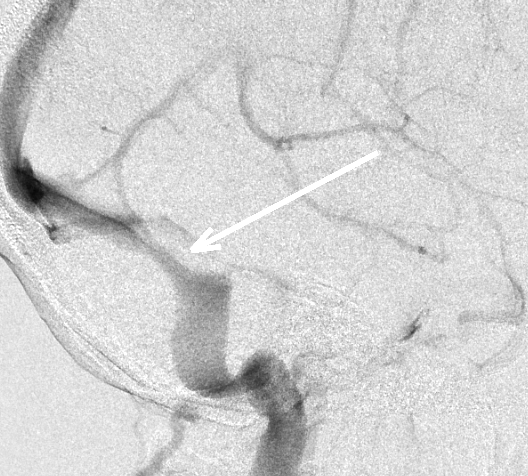

Intracranial venous stenosis prior to stent placement (above) and after (below)

While all causes of pseudotumor cerebri have yet to be been identified, it has been revealed that some cases are the result of intracranial venous outflow stenosis. This narrowing of veins prevents adequate blood drainage from the brain. “If the blood can’t get out, it backs up, and the pressure builds,” says Liu. “Over time, this can lead to vision loss or other neurologic problems.”

Using Stents to Reduce Pressure

For patients with pseudotumor cerebri resulting from intracranial venous stenosis, Liu and his colleagues at UVA are now utilizing endovascular venous stent placement with positive, longer-term results. According to Liu, this technique has slowly been gaining acceptance in the past decade, and UVA is working to prove that stent placement actually reduces a patient’s intracranial pressures.